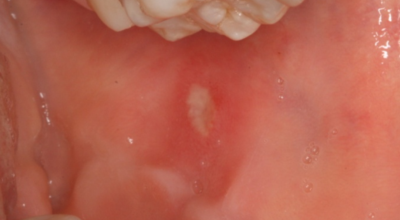

입안에 우유 순수하지 않은 물질 같은 흰 막이 생기고 통증이 있으면, 구강 칸디다증을 의심할 수 있어요. 구강 칸디다증은 '아구창'이라고 부르기도 하고, 입안에 우유 이물질 같은 흰 막이 생기면서 음식을 삼킬 때 통증을 동반해요.구강 칸디다증을 일으키는 칸디다는 사람의 입, 소화기관, 질, 피부에 정상적으로 살고 있는 진균인데, 면역기능이 정상인 사람에게는 아무런 이상을 유발하지 않아요.

그러나, 면역기능이 줄어들게 되면 칸디다증을 나타나게 할 수 있답니다. 각별히 당뇨병, 결핵, 혈액질환, 면역질환, 악성종양을 지니고 있거나, 노약자, 어린 아이, 임산부 등 체력이나 면역력이 떨어져 있는 사람들, 틀니를 활용하던가, 구강 건조증이 있는 사람, 항생제를 장기 섭취하는 사람에게 생기기 쉬워요.